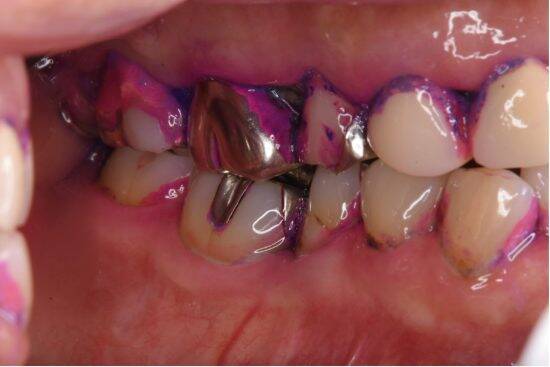

実は、この考え方こそが医療費を膨らませる元凶。歯や歯茎のトラブルは、早期に対策することで治療費も時間も最小限に抑えられます。逆に、放置して重症化すると、治療費は一気に跳ね上がるだけでなく、全身の健康にも悪影響を及ぼします。

歯の治療は想像以上に高額となるケースが多いです。

40代、50代の働き盛りの時期から入れ歯を使用されている患者さんもいます。入れ歯は見た目にも影響しますが、これからの人生をずっと入れ歯がないと食事がしづらくなることが一番の問題です。

歯を失い、入れ歯がどんどん増えていくと、ご飯も食べられないものが出てきて、楽しみがなくなっていくのは大きく生活の質を低下させます。食は人生の大きな楽しみであり、健康な歯がないと、思うように楽しめないのです。